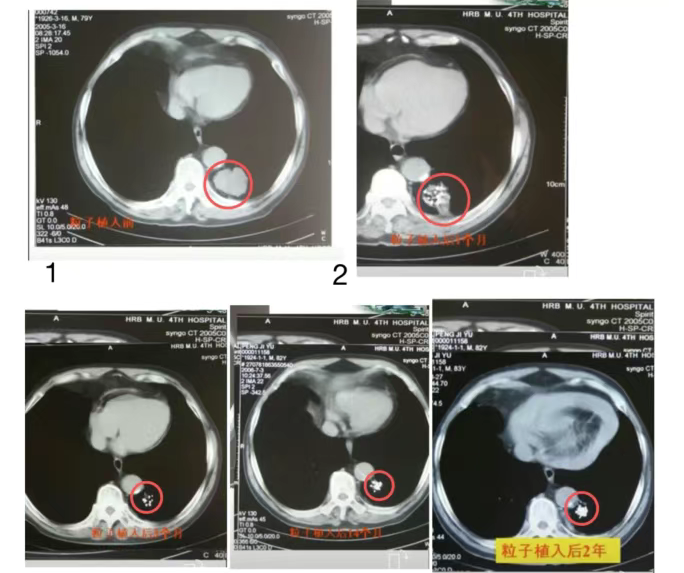

简单来说,就是在影像引导下(如 CT、超声等),将直径约几毫米的碘-125放射性粒子,按照术前精确规划,直接植入肿瘤内部或肿瘤周围,让放射线在局部持续发挥作用,从而达到控制或杀灭肿瘤细胞的目的。

碘-125粒子释放的是低能γ射线,射程短(主要作用于肿瘤及其邻近区域);半衰期约60天;持续、稳定、缓慢释放辐射剂量。这使它在治疗过程中,对周围正常组织的影响相对可控。

粒子植入后不会“立刻见效”,而是通过持续低剂量辐射,逐步破坏肿瘤细胞的DNA,抑制其分裂和生长。

2. 持续、稳定的低剂量照射

粒子可在体内持续释放低剂量γ射线,使肿瘤细胞在较长时间内处于受照状态,更有利于抑制肿瘤细胞增殖,符合肿瘤生物学特点。